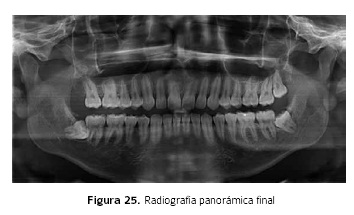

Radiográficamente se obtiene en sentido horizontal una distalización de 3 mm en el cuadrante superior derecho, medido desde la superficie distal del primer molar con referencia a una perpendicular de la horizontal de Frankfurt que pasa por PTM (Fosa Pterigo Maxilar) (Tabla 1). En sentido vertical se produce una intrusión de 2 mm del molar superior con respecto al plano Biespinal (Figura 26).

Con respecto a la inclinación del incisivo superior se encuentran cambios angulares de 5 grados con referencia al plano Biespinal (Figura 24,25).